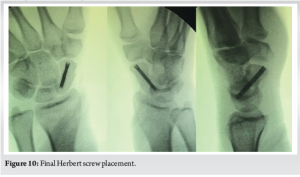

Once the trajectory is deemed satisfactory, a guidewire is inserted through the needle. The needle is then withdrawn, and a cannulated drill is used to prepare the tract. The Herbert screw is inserted in standard fashion.[Fig. 10]

For a successful scaphoid surgery, a few key technical steps are crucial: achieving a precise entry point, ensuring that the guide wire is placed accurately along the central axis of the scaphoid in both antero-posterior [Fig. 6,7] and Lateral Views [Fig. 8,9] for optimal trajectory, and then carefully drilling over the guide wire followed by the correct placement of the Herbert screw along the same path[Fig. 10]. Each step demands meticulous execution to ensure proper compression, stability, and ultimately, a good functional outcome.

Final placement of the screw.[Fig. 10]